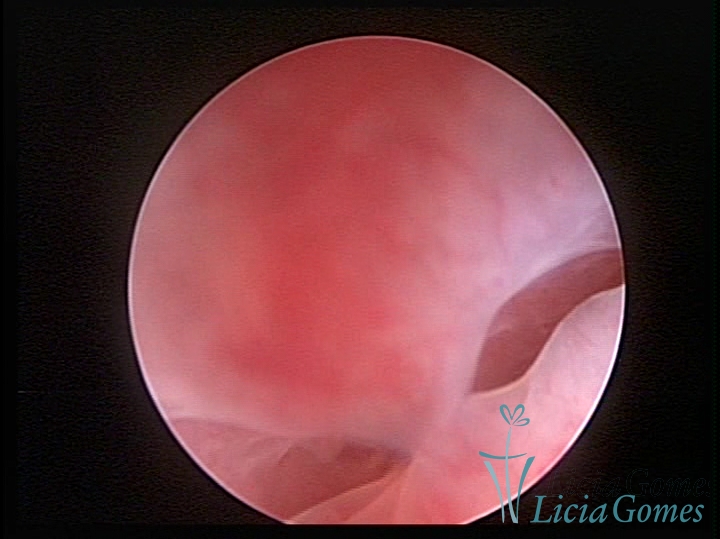

FIBROUS SYNECHIA

Uterine synechiae are scars (adherence) between the surface of the uterine walls, which may occur after the surgical procedure, uterine curettage, or after an inflammatory process in the uterine cavity (endometritis), which may lead to menstrual changes, infertility and obstetric complication such as abortion and premature birth.